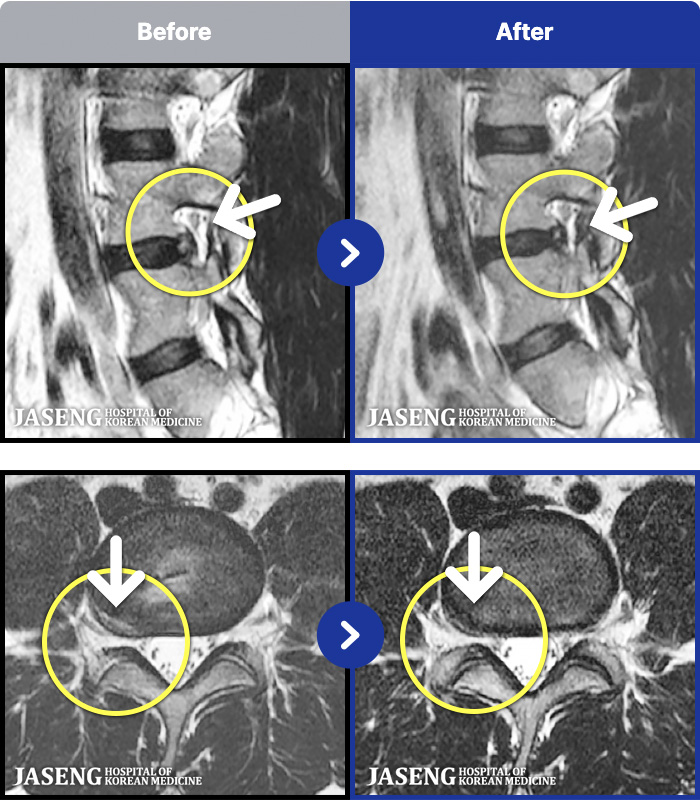

[] 23.11.11~25.06.04

ȯںп Ǹ ǿ ԿǾ, ο ġ ۿ Ƿ ġḦ Ͻñ ٶϴ.